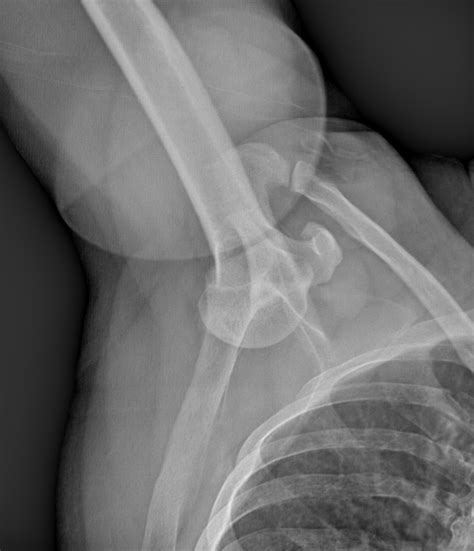

Diagnosis of Inferior Shoulder Dislocation

Diagnosing an inferior shoulder dislocation involves a combination of physical examination and imaging tests. The diagnostic process typically includes:

• Physical examination: A healthcare provider will assess the shoulder for deformity, swelling, and range of motion.

• X-rays: Imaging tests can confirm the dislocation and rule out fractures or other injuries.

• CT scan or MRI: These advanced imaging techniques may be used to evaluate the extent of the injury and plan treatment.

Accurate diagnosis is crucial for determining the appropriate course of treatment and ensuring a successful recovery.

• inferior shoulder dislocation xray

• inferior shoulder dislocation xr